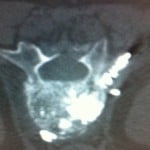

The CT scan of the treated vertebrae performed at the end of the procedure identified cement leakage along needle route into paraspinal soft tissues in seven patients (Fig. 1). Five patients were women and two were men, and the mean age ± SD was 81 ± 6 years (range, 68-88 years). These patients were treated for painful vertebral compression fractures that were secondary to osteoporosis (n = 5) and multiple myeloma (n = 2). Vertebroplasty was performed on the following vertebrae: D12 (n = 2), L1 (n = 3), L2 (n = 1) and L3 (n = 1), using a single posterolateral (laterovertebral or intercostovertebral) route.

Figure 1. The CT scan performed at the end of the vertebroplasty procedure identified cement leakage into the paraspinal soft tissues.